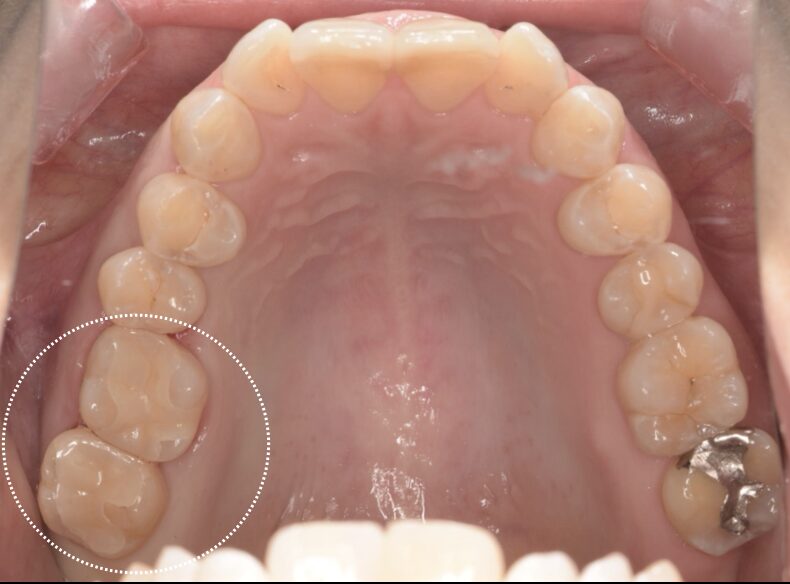

セラミック / 審美歯科

銀歯をセラミックインレー、樹脂での治療(メタルフリー)

Before

| 治療内容 | セラミックインレー |

| 治療期間・治療回数 | 2回 |

| 治療費用 | 143000円(税込) |

| 備考 | 30代 女性 |